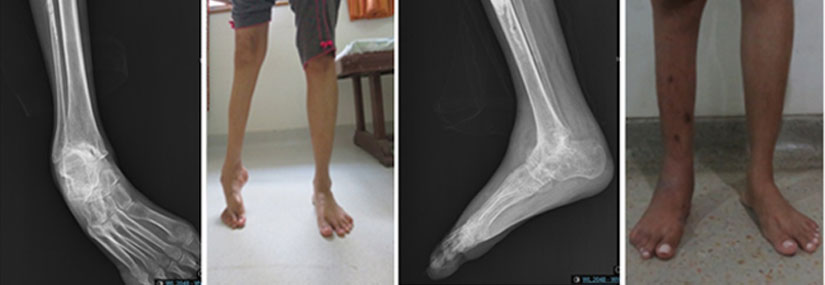

Deformity Correction

Bone deformity correction is a surgical and non-surgical approach to address abnormalities in bone structure and alignment. These deformities can arise from congenital conditions, trauma, diseases, or other factors. The goal of correction is to restore normal function, improve appearance, and alleviate pain or discomfort.

• Postoperative imaging (e.g., X-rays) to assess the success of the correction.